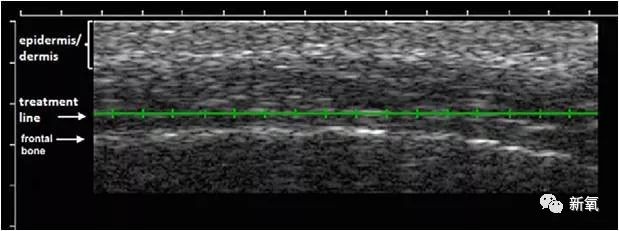

美版超声刀的核心在于独一份的Deepsee技术。

这个技术的特点在于治疗头有B超功能,可在操作屏上看到实时真实的皮肤超声影像。下图中的绿线,就是操作中探头挨着皮肤后,这个光头的作用层面。

医生可以根据屏幕的显示判断是否作用在了目标层上,以及能看清皮下的各层面厚度,进而更好更精准的做到有效的治疗。